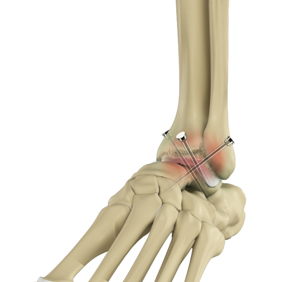

- The joints are then fused together with the help of screws, wires, plates, or rods.

- Bone grafting may be performed in cases of substantial bone loss. This is done using a graft taken from another part of your body (autograft) or from donor tissue (allograft).

- Your surgeon will also perform any other required repairs in the treatment area.

- Finally, the overlying soft tissue and skin are closed with sutures and sterile bandages are applied.